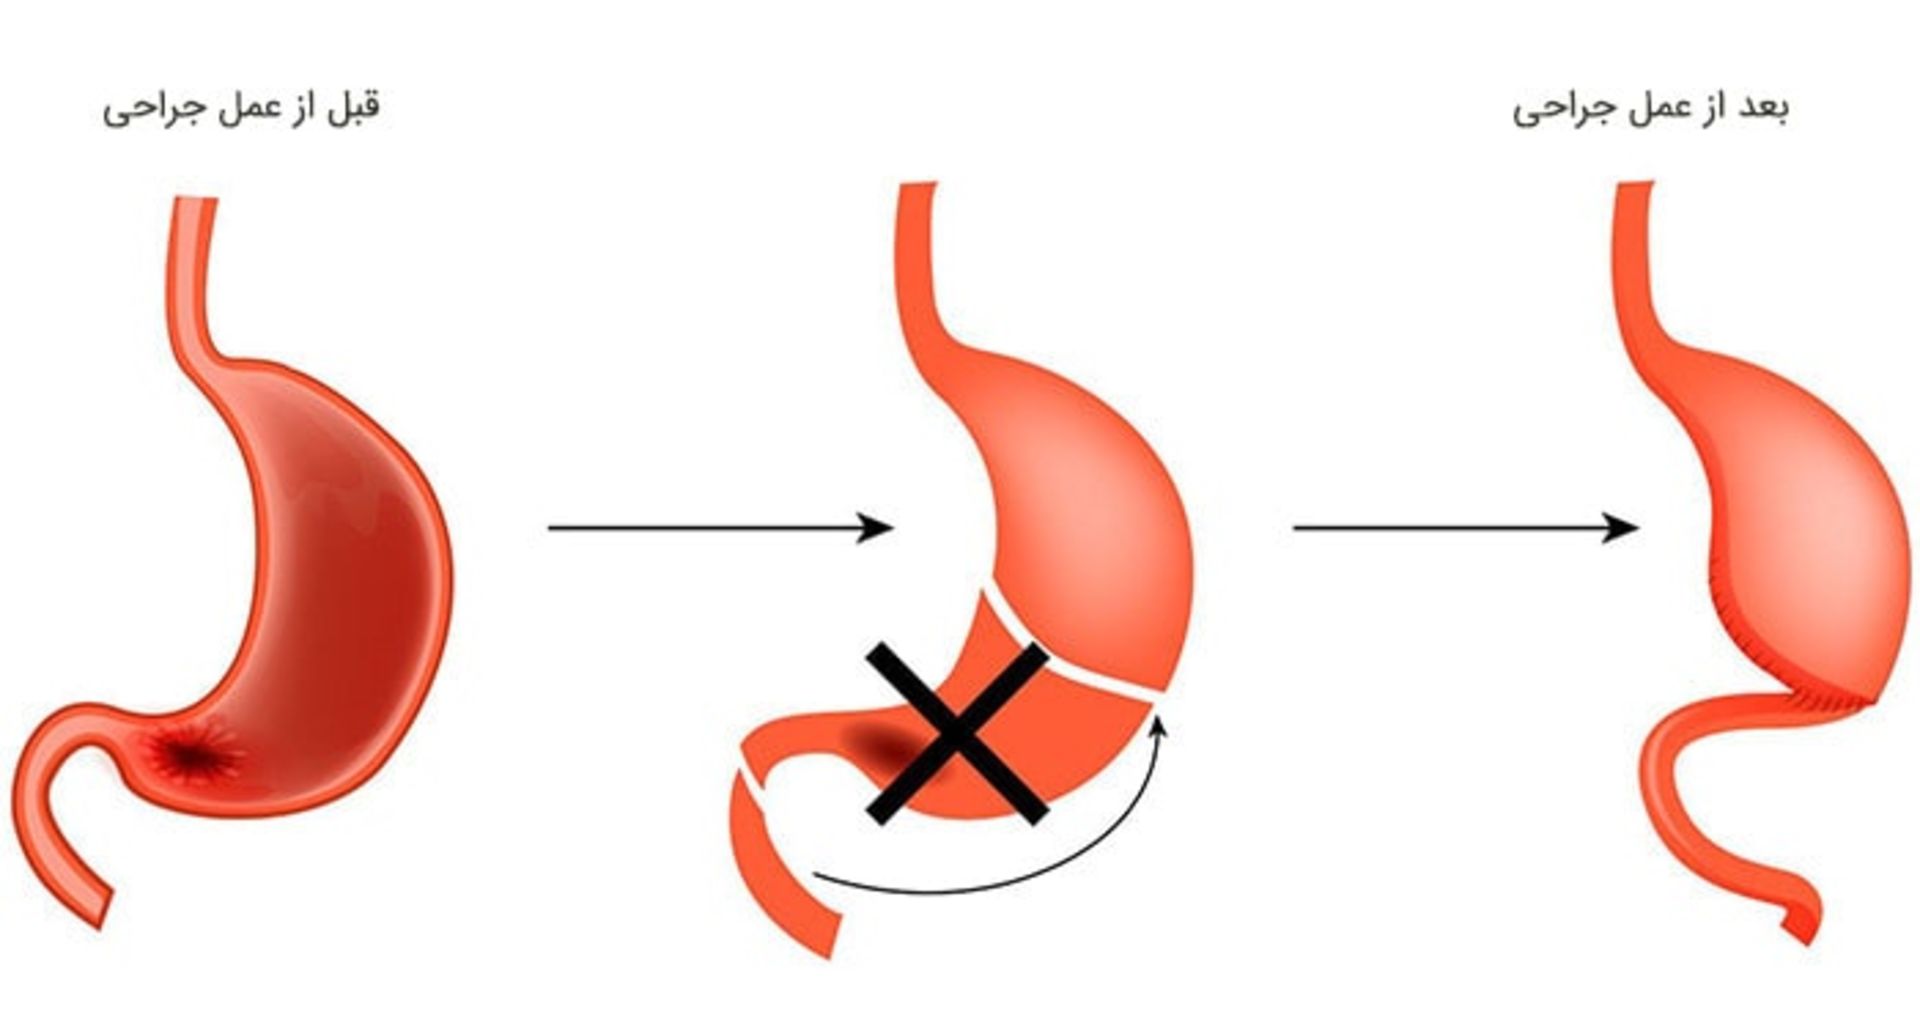

جراحی معده جزئی

اغلب این عمل درصورتی توصیه میشود که سرطان تنها در بخش تحتانی معده بروز کرده باشد. از این روش کمتر برای سرطانهایی که تنها در بخش فوقاتی معده بروز کردهاند، استفاده میشود. تنها قسمتی از معده و گاهی همراهبا بخشی از مری یا بخش ابتدایی رودهی کوچک (دوازدهه) برداشته میشود. سپس بخش باقیماندهی معده مجددا متصل میشود. بخشی از اومنتوم (لایهای از بافت چربی که معده و رودهی کوچک را میپوشاند) نیز همراهبا گرههای لنفاوی مجاور و احتمالا طحال و بخشهایی از دیگر اندامهای مجاور نیز جدا میشود.

جراحی معده کلی

این عمل درصورتی انجام میشود که سرطان در کل معده پخش شده باشد. این روش همچنین اغلب درصورتی که سرطان در بخش فوقانی معده نزدیک مری اتفاق افتاده باشد، نیز توصیه میشود. پزشک جراح کل معده، گرههای لنفاوی مجاور و اومونتوم را برمیدارد. طحال و بخشهایی از مری، رودهی کوچک، پانکراس یا دیگر اندامهای مجاور نیز ممکن است برداشته شود. سپس انتهای مری به رودهی کوچک متصل میشود. این کار موجب میشود غذا از مری وارد رودهی کوچک شود.